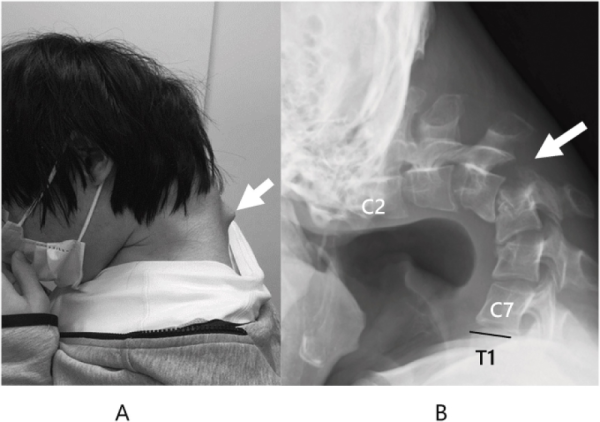

Αποτέλεσμα αυτής της στάσης ήταν να αναπτυχθεί ένα εξόγκωμα στον αυχένα, ενώ ο ίδιος έχασε πλήρως την ικανότητα να σηκώνει το κεφάλι του. Η κάμψη ήταν τόσο προχωρημένη, που το πηγούνι του ακουμπούσε μόνιμα στο στήθος.

Το 2023, ο νεαρός άρχισε να υποφέρει από αφόρητο πόνο στον αυχένα και δυσκολία στην κατάποση, η οποία προκάλεσε ταχεία απώλεια βάρους. Οι ιατρικές εξετάσεις αποκάλυψαν έντονη παραμόρφωση των αυχενικών σπονδύλων, καθώς και βλάβη στην ανώτερη σπονδυλική στήλη – συνέπειες της μακροχρόνιας καταπόνησης και υπερέκτασης των μυών του αυχένα.

Αρχικά οι γιατροί επιχείρησαν να αντιμετωπίσουν την κατάσταση με αυχενικούς νάρθηκες, όμως όταν ο ασθενής ανέφερε μούδιασμα στην περιοχή του λαιμού, η ομάδα αποφάσισε να προχωρήσει σε χειρουργική αποκατάσταση. Οι επεμβάσεις περιελάμβαναν την αφαίρεση τμημάτων κατεστραμμένων σπονδύλων και ουλώδους ιστού, καθώς και την τοποθέτηση βιδών και μεταλλικών ράβδων για την ευθυγράμμιση και σταθεροποίηση του αυχένα.